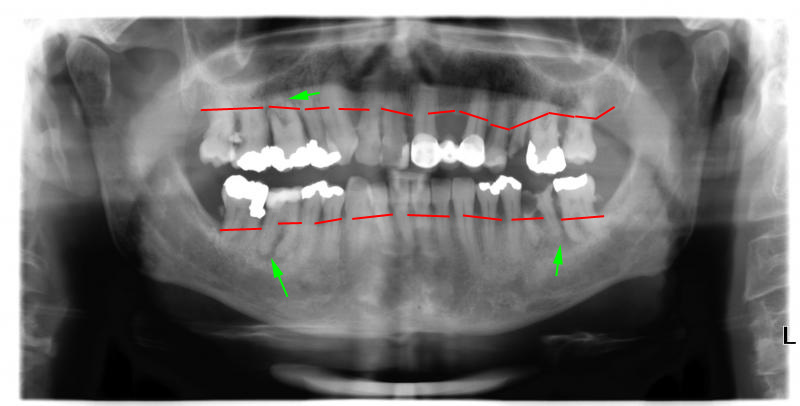

[IMG]https://www.denta-beaute.at/zahnforum/attachments/ddr-belsky/1705d1518966033-gefaehrlichkeit-restaurationsmaterialien-panorama_15012018.jpg[/IMG]

rot ist der knochen wie er jetzt ist, der sollte ca. 1mm unter der schmelz zement grenze sein (das ist dort, wo z.b. deine undichten zahnkronen enden).

bei dir ist er unterhalb des wurzelstammes, deswegen sind die furkationen vermutlich alle offen. dazu paßen auch die beherdungen (grüne pfeile). die aufzählung der wurzelreste und des massiven zahnsteines habe ich mir erspart, denn das sieht sogar steve wonder und da du dich ja soviel damit beschäftigt hast, wirst du es im röntgen auch sehen.

grüne pfeile, der knochen wird durch die entzündung abgebaut, die röntgenstraheln gehen leichter hindurch und somit wird das bild dunkel.

Der grüne Pfeil auf #36 entspricht interessanterweise genau meinen Beobachtungen .

Daß zwischen 36+37 die Entzündung sein müßte !

ZA begründete die der Parulis vorausgehende Entzündung mit dem ‘Furkations-‘Loch’ ,

Die Aufhellung auf 46 ist eine Folge der Überlastung durch langes einseitiges Kauen

– um 36 nicht unnötig zu beschädigen . Auf 14? hab ich keine solchen Empfindungen .